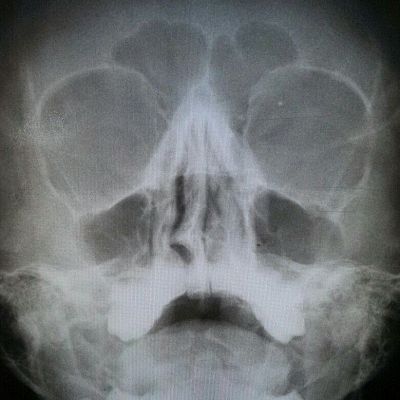

Как же быть в данной ситуации? Никак! «Если носовое дыхание вас устраивает, то нет повода для беспокойства, - говорит заведующий ЛОР-отделением Московской областной больницы имени профессора Розанова В.Н. Кулешов Богдан Юрьевич @kuleshov_lor - Но стоит помнить, что данная патология может начать себя проявлять с годами - появится затруднение носового дыхания, чувство неполноты вдыхания носом. И пациент задаёт вопрос: «Так раньше нос ведь дышал? Что случилось? А причиной этому служит развитие спутника деформации перегородки носа – хронического гипертрофического ринита. Здесь есть один порочный круг, который приводит к данной патологии. Наш нос выполняет функцию кондиционера – согревает, очищает и увлажняет воздух. В случае, когда перегородка носа искривлена в одну сторону, то поток воздуха больше проходит через ту половину, в которой нет деформации. В связи с этим на слизистую нижних носовых раковин идёт большая нагрузка, и для того чтобы согреть весь поступающий воздух, раковина начинает гипертрофироваться (увеличиваться в размере), и в итоге это приводит к сужению носовых ходов. Увеличивается нагрузка на другую половину… И порочный круг замыкается».